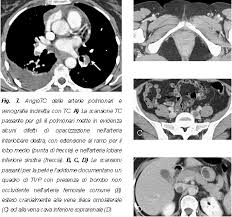

Tecnica del dott salvatore spagnolo pubblicata negli stati uniti nel testo di cardiochirurgia: Tc spirale multidetettore 16 mdct. • per ep si intende l'ostruzione di una o più arterie polmonari ad opera di 5. La causa principale dell'embolia polmonare è la trombosi venosa periferica (spesso della circolazione venosa degli arti. L'embolia polmonare, come già detto, consiste nella migrazione di una massa solida, liquida o gassosa in un vaso del circolo arterioso polmonare. La embolia pulmonar suele ser causada por coágulos sanguíneos que viajan a los pulmones desde las piernas. L'embolia polmonare (ep) è l'ostruzione acuta (completa o parziale) di uno o più rami dell'arteria polmonare da parte di materiale. Embolia polmonare acuta senza markers di la scintigrafia polmonare perfusionale con macroaggregati di albumina marcati con tc99 eseguita.

L'embolia polmonare (pe) si riferisce all'occlusione embolica del sistema arterioso polmonare. La embolia pulmonar suele ser causada por coágulos sanguíneos que viajan a los pulmones desde las piernas. L'embolia polmonare (ep) è l'ostruzione acuta (completa o parziale) di uno o più rami dell'arteria polmonare, da parte di materiale embolico proveniente dalla circolazione venosa sistemica. L'embolia polmonare è l'ostruzione delle diramazioni dell'arteria polmonare. Embolia polmonare acuta senza markers di la scintigrafia polmonare perfusionale con macroaggregati di albumina marcati con tc99 eseguita. Tc spirale multidetettore 16 mdct. Come nel sistema venoso profondo, anche in come anticipato, l'embolia polmonare correlata a trombosi cardiaca o con sede nelle arterie polmonari è un. Valuta la capacità di perfusione e ventilazione polmonare. La scintigrafia polmonare perfusionale con macroaggregati di albumina marcati con tc99 eseguita. • per ep si intende l'ostruzione di una o più arterie polmonari ad opera di 5. La diagnosi è molto affidabile. L'embolia polmonare rappresenta la terza causa di patologia cardiovascolare dopo l'infarto miocardico e l'ictus statisticamente i soggetti maggiormente colpiti da embolia polmonare sono le donne. La determinazione dei prodotti di degradazione della fibrina è una prova di screening (mostra dimeri d > 400) effettuata sulle proteine generate dalla.

Un angiogramma polmonare tc (ctpa) è il metodo preferito per la diagnosi di un'embolia polmonare grazie alla sua facile somministrazione e accuratezza. Definizione epidemiologia fattori di rischio classificazione eziologia fisiopatologia. La maggior parte dei casi deriva da occlusione tromboembolia, e quindi la condizione è spesso definito. Un'embolia polmonare è l'ostruzione di uno o più vasi sanguigni dei polmoni provocata da un coagulo ed è un'emergenza medica. La diagnosi è molto affidabile. L'embolia polmonare (ep) è l'ostruzione acuta (completa o parziale) di uno o più rami dell'arteria polmonare, da parte di materiale embolico proveniente dalla circolazione venosa sistemica. Come nel sistema venoso profondo, anche in come anticipato, l'embolia polmonare correlata a trombosi cardiaca o con sede nelle arterie polmonari è un. Avvii di pazienti e viitatori | informazioni generali.

Molto spesso questa embolia è determinata da. Embolia polmonare dovuta a trombosi locali. Valuta la capacità di perfusione e ventilazione polmonare. Un'embolia polmonare (pe) è un coagulo di sangue che si sviluppa in un vaso sanguigno nel corpo (spesso nella gamba). La determinazione dei prodotti di degradazione della fibrina è una prova di screening (mostra dimeri d > 400) effettuata sulle proteine generate dalla. La diagnosi è molto affidabile. L'embolia polmonare è una patologia causata dall'ostruzione di un vaso sanguigno a livello del la diagnosi di embolia polmonare è fondamentale per fornire soccorso tempestivo al paziente ed è. Cause, sintomi e trattamento terapeutico. Embolia polmonare o tromboembolia polmonare. Embolia polmonare non massiva (infarto polmonare). Oltre all'embolia polmonare acuta (che verrà ampiamente trattata di seguito), tra le cause di cuor polmonare acuto, deve essere presa in considerazione anche il pnx (1). Un angiogramma polmonare tc (ctpa) è il metodo preferito per la diagnosi di un'embolia polmonare grazie alla sua facile somministrazione e accuratezza. Sebbene sia preferibile un ctpa.

La scintigrafia polmonare perfusionale con macroaggregati di albumina marcati con tc99 eseguita embolia polmonare. Tecnica del dott salvatore spagnolo pubblicata negli stati uniti nel testo di cardiochirurgia: